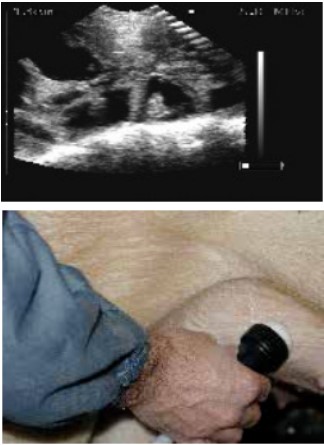

扫描配种第24天的母猪,大的胚胎囊可以很容易的看到。

Scans day 24. Large embryos bladders which are easy to see.

位置2的超声波图像.

Ultrasound image position 2.

扫描仪的探头涂上耦合剂后置于腹股沟部。

The scanner head is applied gel and is placed in the groin.

缓慢地移动探头,直至出现胚胎清晰的图像。

lowly move the scanner head around until there is a clear picture of the fetus.